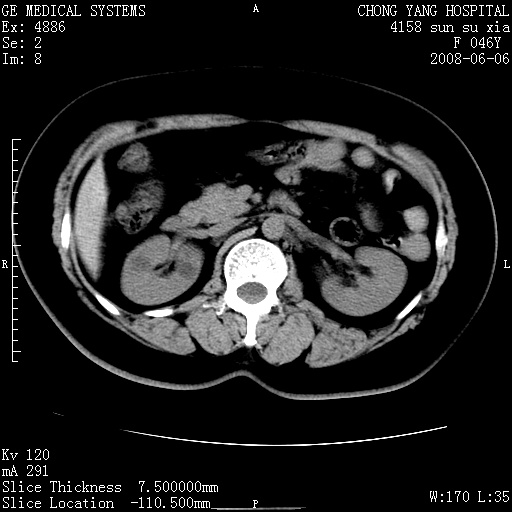

标题: CT13886:F 40Y, 外侧的CT值-60 内侧的25HU. 未作增强 [打印本页]

标题: CT13886:F 40Y, 外侧的CT值-60 内侧的25HU. 未作增强

考虑:右肾错构瘤。

右肾平滑肌脂肪瘤并肾囊肿

右肾血管平滑肌脂肪瘤并肾囊肿(后者请排除容积效应,可结合超声)

右肾血管平滑肌脂肪瘤并肾囊肿(后者请排除容积效应,可薄层扫描或结合超声)

根据影像表现,基本可确诊!